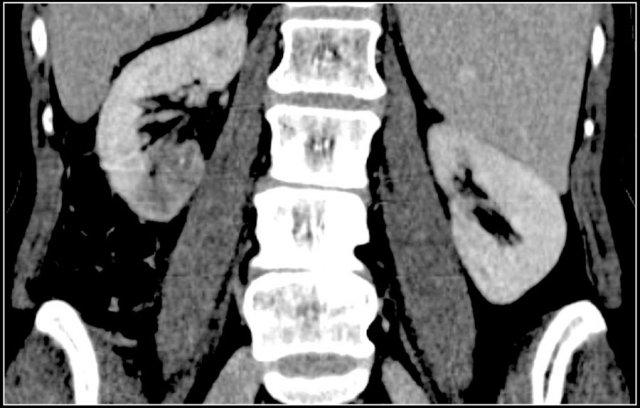

TCC thường gặp nhất ở bể thận, dưới dạng khối u bề mặt độ thấp, tạo thành một khối trong lòng khu trú tại hệ thống đài bể thận.

Khoảng 15% các trường hợp TCC thuộc loại xâm lấn hơn với kiểu phát triển thâm nhiễm, làm thay đổi cấu trúc vùng của xoang thận và nhu mô thận lân cận, nhưng không làm thay đổi đường bờ thận.

TCC là tổn thương điển hình dạng hạt đậu (xem hình).

TCC khó phát hiện trên hình ảnh CT không tiêm thuốc cản quang.

Thì thận sinh (nephrogenic phase) là thì tối ưu để thấy rõ ranh giới giữa TCC và nhu mô thận bình thường có ngấm thuốc.

Hình ảnh thì bài tiết cho thấy các bất thường của hệ thống đài bể thận như đài thận giãn, đài thận bị khối u lấp đầy hoặc đài thận không ngấm thuốc do khối u thâm nhiễm.